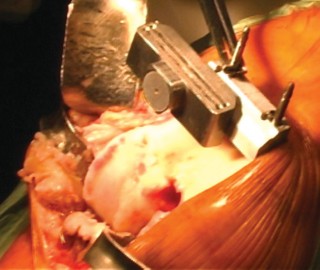

الخطوة 1: التحضير الأولي والوصول إلى المفصل

- المعدات: يتم استخدام حامل للساق لتثبيت القدم والكاحل، مما يتيح للجراح سهولة تحريك الساق أثناء العملية.

- وضع المريض: يُوضع المريض على ظهره على طاولة العمليات.

- الوزن الزائد: قد تتطلب حالات المرضى الذين يعانون من السمنة المفرطة أحجامًا أكبر من رباط ضاغط (Tourniquet) لضمان التحكم الأمثل في النزيف أثناء الجراحة، وهذا اعتبار مهم يضعه الجراح في الحسبان.

- الرباط الضاغط: يُوضع رباط ضاغط حول الجزء العلوي من الفخذ للتحكم في تدفق الدم وتقليل النزيف أثناء الجراحة.

الوصول إلى المفصل (الشقوق):

يستخدم الأستاذ الدكتور محمد هطيف عادةً نهجًا جراحيًا طفيف التوغل (abbreviated trivector approach) للوصول إلى الركبة.

- يتم عمل شق جراحي يبدأ من الجزء الإنسي للحدبة الظنبوبية ويمتد إلى الجزء العلوي من الرضفة.

- يتم فصل ارتباط العضلة المتسعة الإنسية عن وتر العضلة الرباعية، مع الحرص على عدم تجاوز 3 سم فوق القطب العلوي للرضفة.

- يتم رفع غشاء الأنسجة الرخوة الإنسي بعناية وصولاً إلى الزاوية الخلفية الإنسية للركبة.

- يتم إزالة جزء من الوسادة الدهنية للرضفة.

- تُدفع الرضفة بعد ذلك إلى الميزاب الجانبي وتُثنى الركبة لزيادة كشف المفصل.